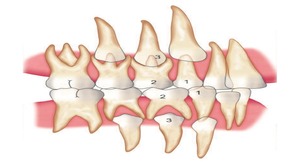

Space Maintainer

Keeps space for permanent teeth after premature tooth loss.

Serial Extraction

Guides proper alignment by removing selected teeth early.